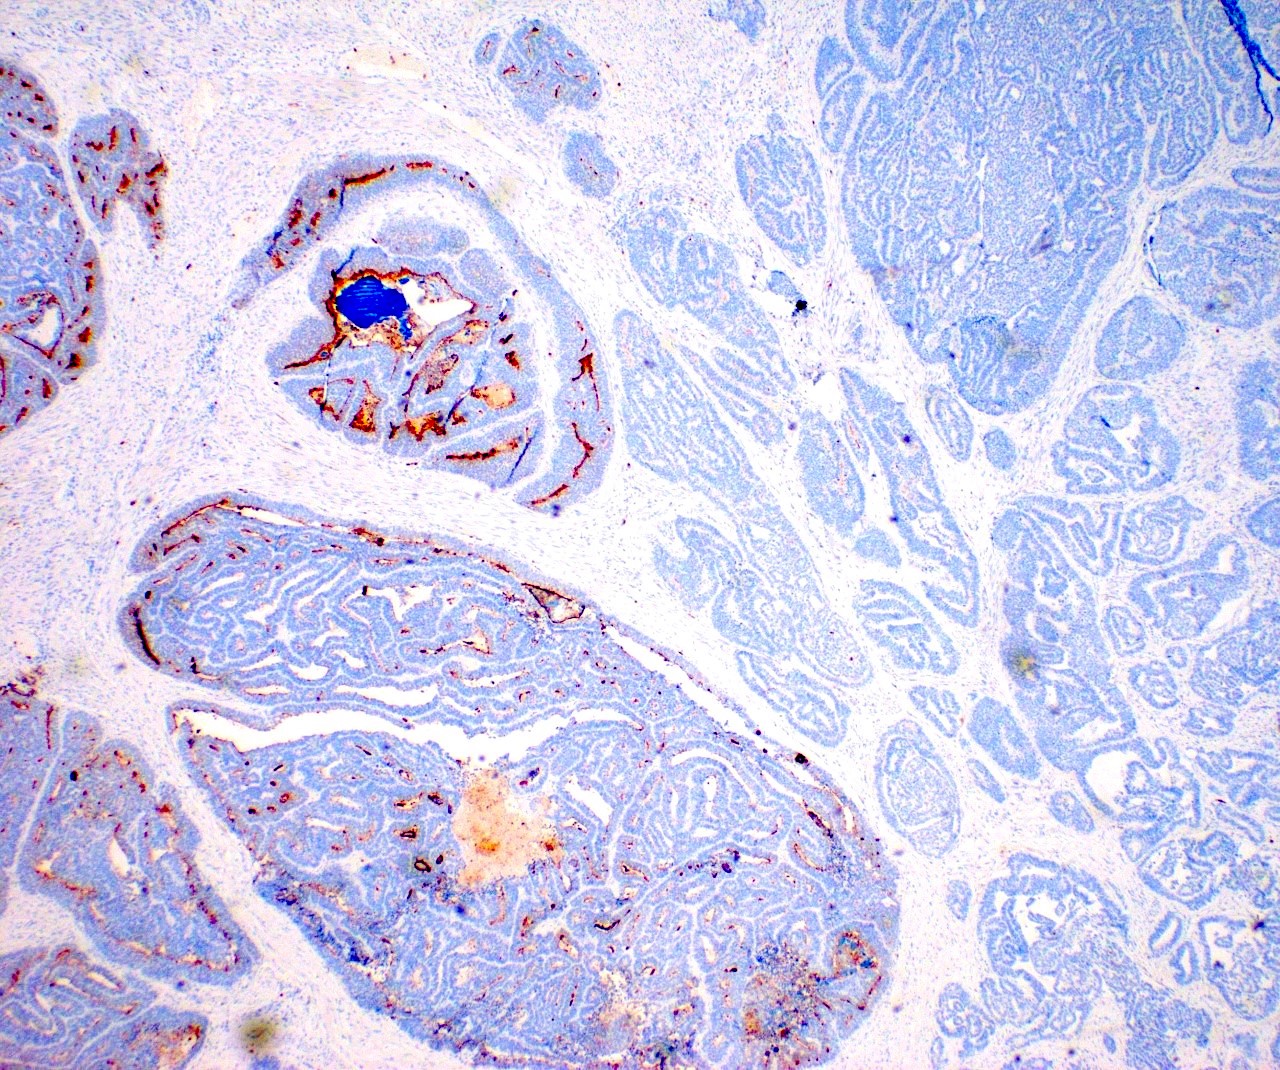

Microscopic (histologic) images

Contributed by Daniel Graham, M.D., Adele Wong, M.B., B.Ch., B.A.O. and Lucy Ma, M.D.